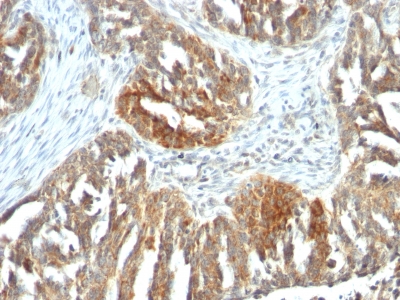

Fig. 1: Formalin-fixed, paraffin-embedded human Pancreatic Carcinoma stained with MRP3 Mouse Monoclonal Antibody (ABCC3/2971).

Immunohistochemistry (Formalin-fixed) (1-2ug/ml for 30 minutes at RT)(Staining of formalin-fixed tissues requires heating tissue sections in 10mM Tris with 1mM EDTA, pH 9.0, for 45 min at 95°C followed by cooling at RT for 20 minutes)